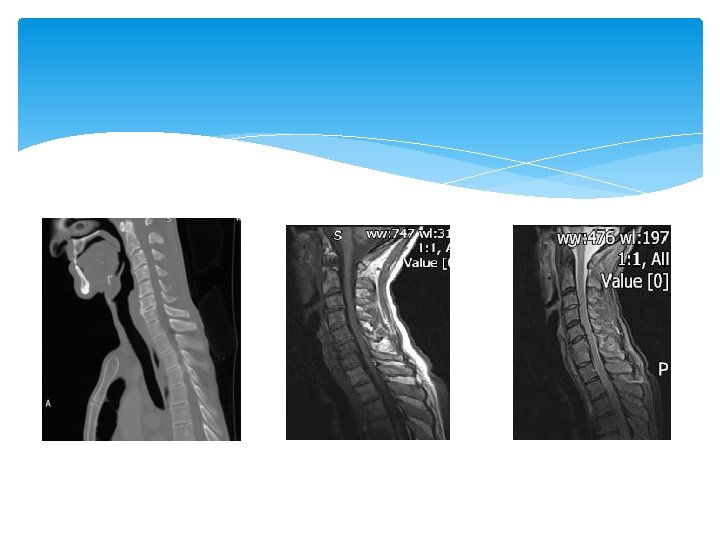

Fractures Vary according to mechanism of injury. May go straight to CT if major trauma. If focal neurology need CT and MRI.

C 1 - Jefferson/ burst fracture Widening of lateral masses on open mouth views. Axial compression.

C 2 -Hangman’s

Peg fracture Flexion/ extension. Can be unstable.

Teardrop Forced extension. Usually neurologically intact

Burst Fracture Axial compression.

Facet joint dislocation- uni/ bilat Flexion/ rotation/ distraction.